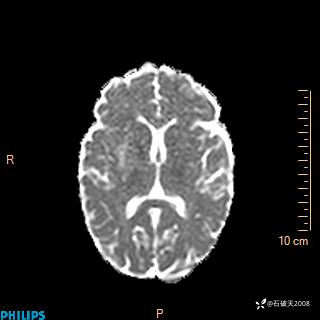

2020.11.14MR

DWI

ADC